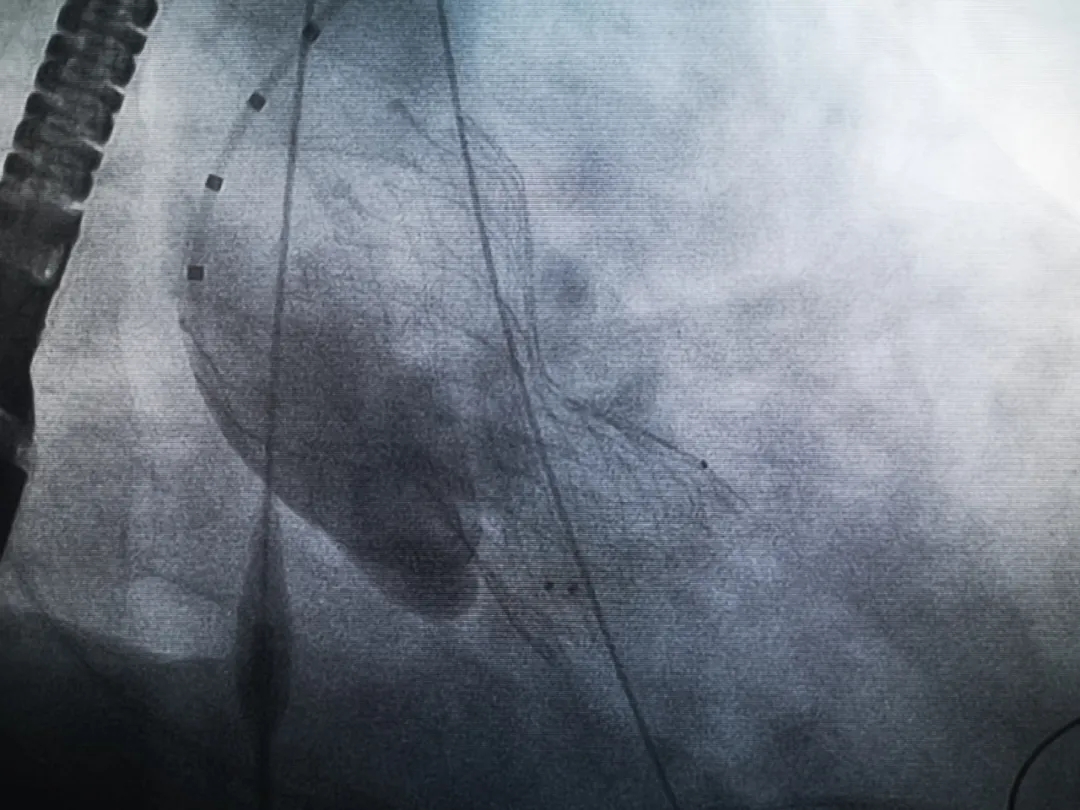

手術(shù)過(guò)程緊張而有序,心臟沒(méi)有停跳,也沒(méi)有太大的血壓波動(dòng);球囊擴(kuò)張的恰到好處,瓣膜釋放之后超聲醫(yī)生的評(píng)估是至關(guān)重要的,因?yàn)槲覀兲崆熬蜏?zhǔn)備了后擴(kuò)張,也準(zhǔn)備了瓣中瓣,甚至還準(zhǔn)備了瓣周漏封堵。所幸的是,超聲診療中心劉夢(mèng)梅醫(yī)生說(shuō):沒(méi)有返流、沒(méi)有瓣周漏,瓣膜形態(tài)良好,跨瓣壓差約17mmHg(相較于術(shù)前的87mmHg還是可以接受的)。瓣膜置入的成功并不是慶祝的時(shí)候,從戰(zhàn)場(chǎng)撤退仍然需要謹(jǐn)慎。由于王子特別胖,腹股溝區(qū)脂肪尤為肥厚,在股動(dòng)脈插管拔除、確認(rèn)搏動(dòng)正常之后,便逐層縫合。同時(shí)為了美觀、縫合之后不至于鼓個(gè)包出來(lái),我們又仔細(xì)剪除了部分脂肪。術(shù)后次日,王子便可以下床活動(dòng)了。